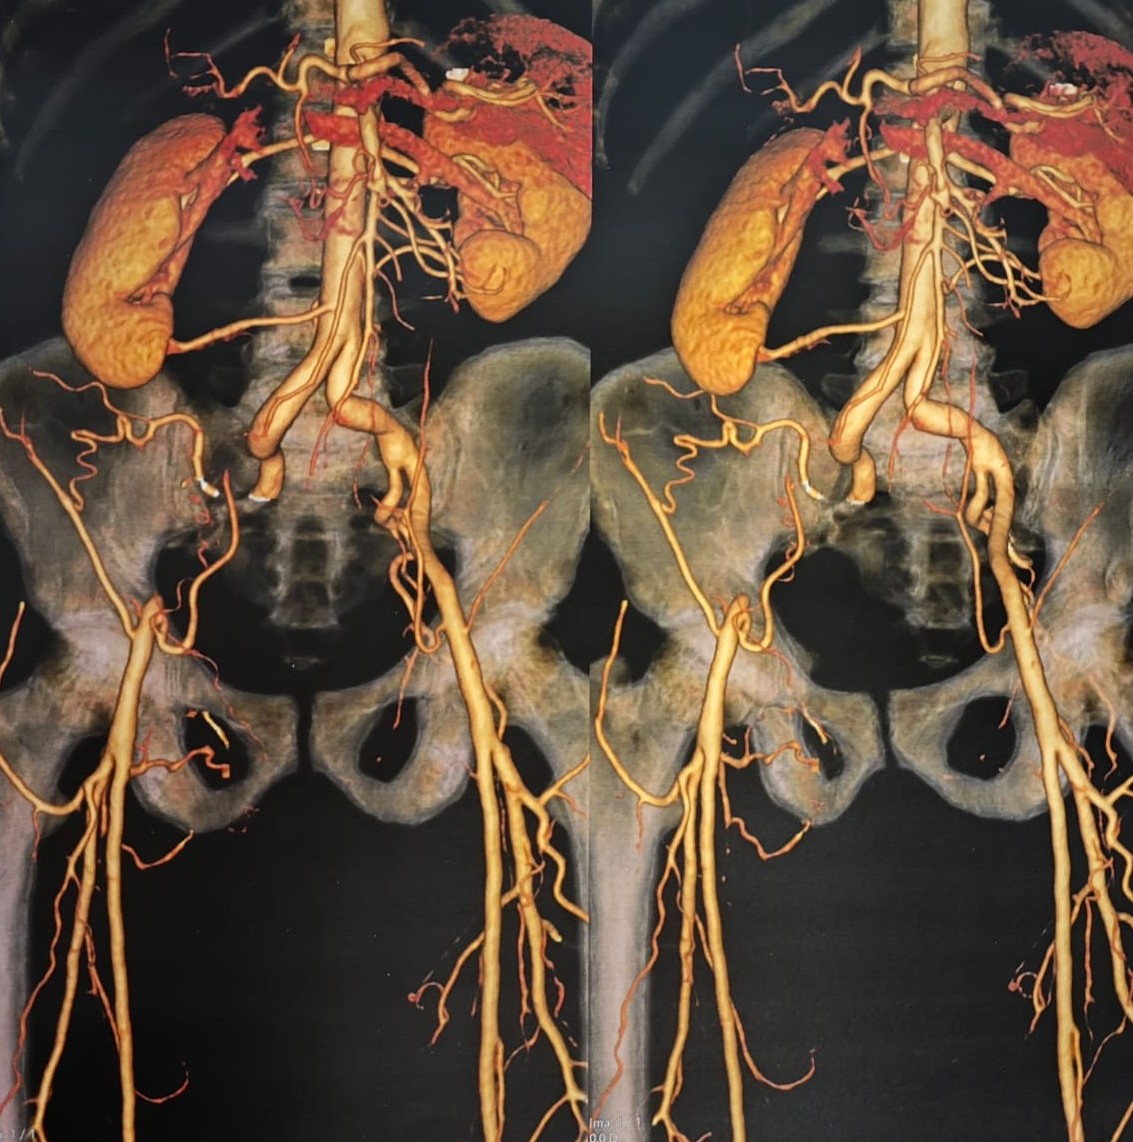

Quando a Perna Desliga: Endofibrose Oclusiva e cirurgia Abdominal Aberta

Minha experiência com a endofibrose da artéria ilíaca externa.